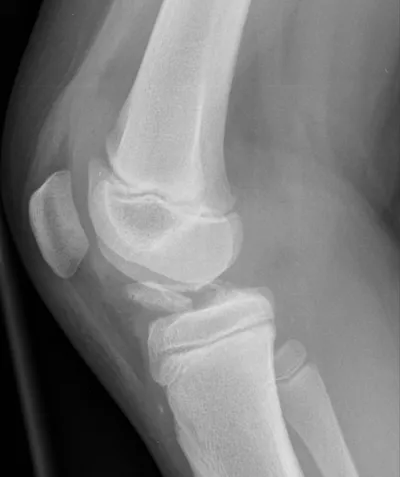

This collection contains 1 radiology images related to lipohaemarthrosis, including various imaging modalities such as X-rays, MRIs, CT scans, and ultrasound images commonly used in medical diagnosis and education.